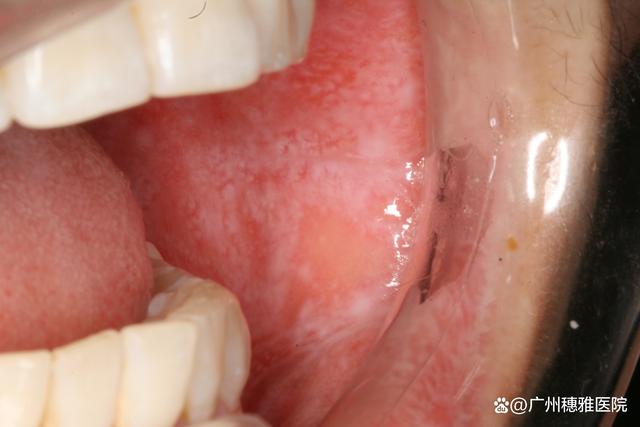

(图片来源网络,侵删)